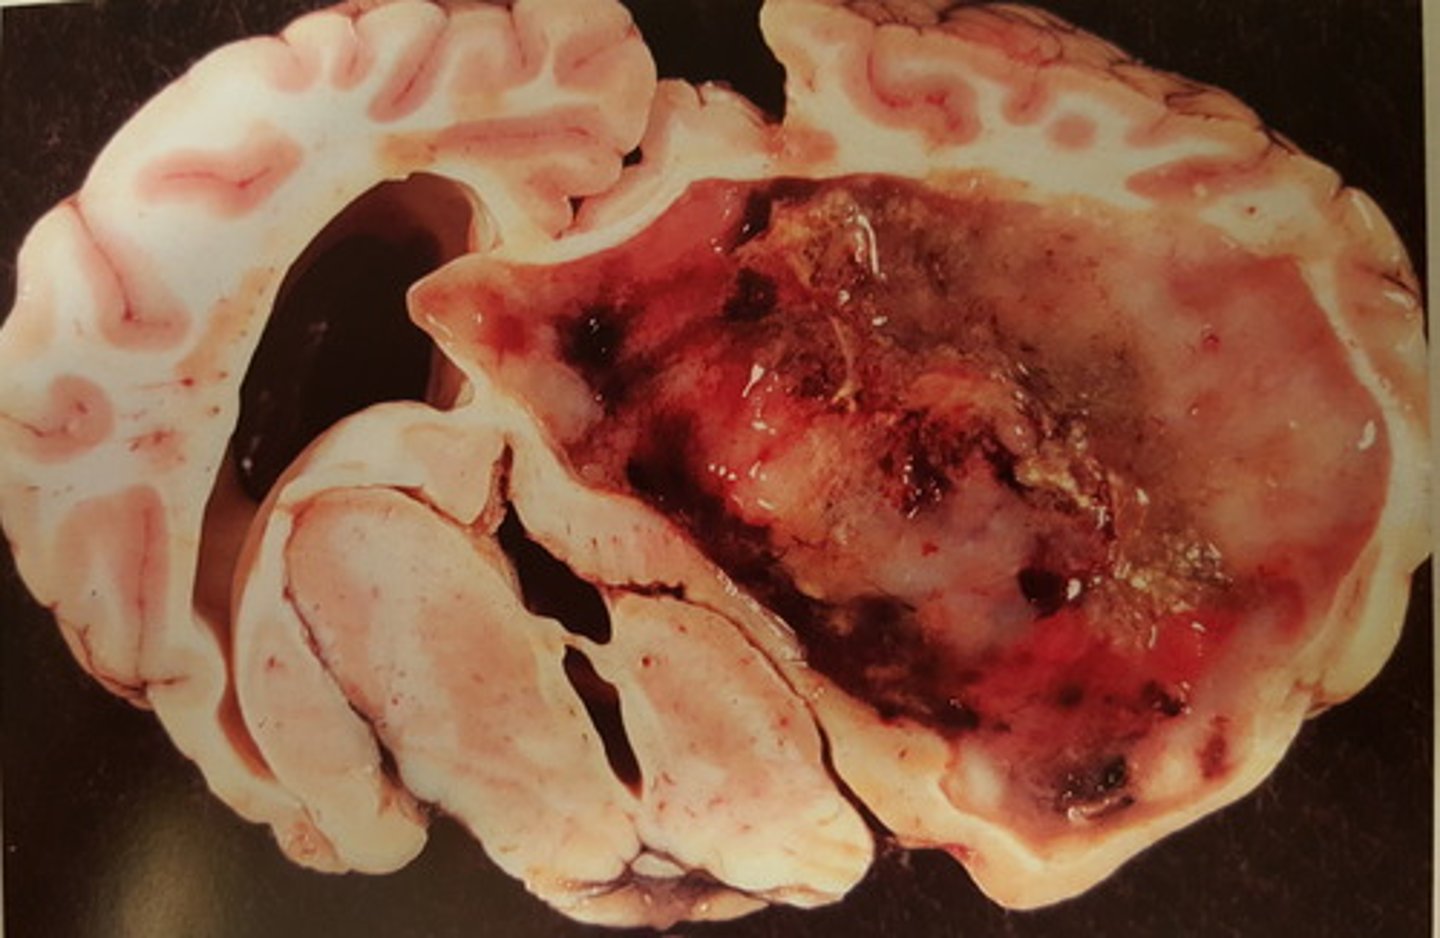

kronisk fokal nekrotiserende meningoencephalitis. hæmatogen

Hjerne fra svin. Patoanatomisk diagnose? patogenesen?

kronisk dissemineret apostematøs encephalitis med abscesdannelse

Hjerne fra okse. Patoanatomisk diagnose?

kronisk dissemineret apostematøs encephalitis. Kan opstå som led i pyæmi

Hjerne fra okse. Patoanatomisk diagnose? Hvordan kan det opstå?

kronisk fokal apostematøs encephalitis. Kan opstå som led i en pyæmi

Mesencephalon hos okse. Patoanatomisk diagnose? Hvordan kan det opstå?

kronisk solitær hjerneabsces. Den kan opstå som led i en pyæmi

Hjerne fra får. Patoanatomisk diagnose? Hvordan kan læsionen opstå?